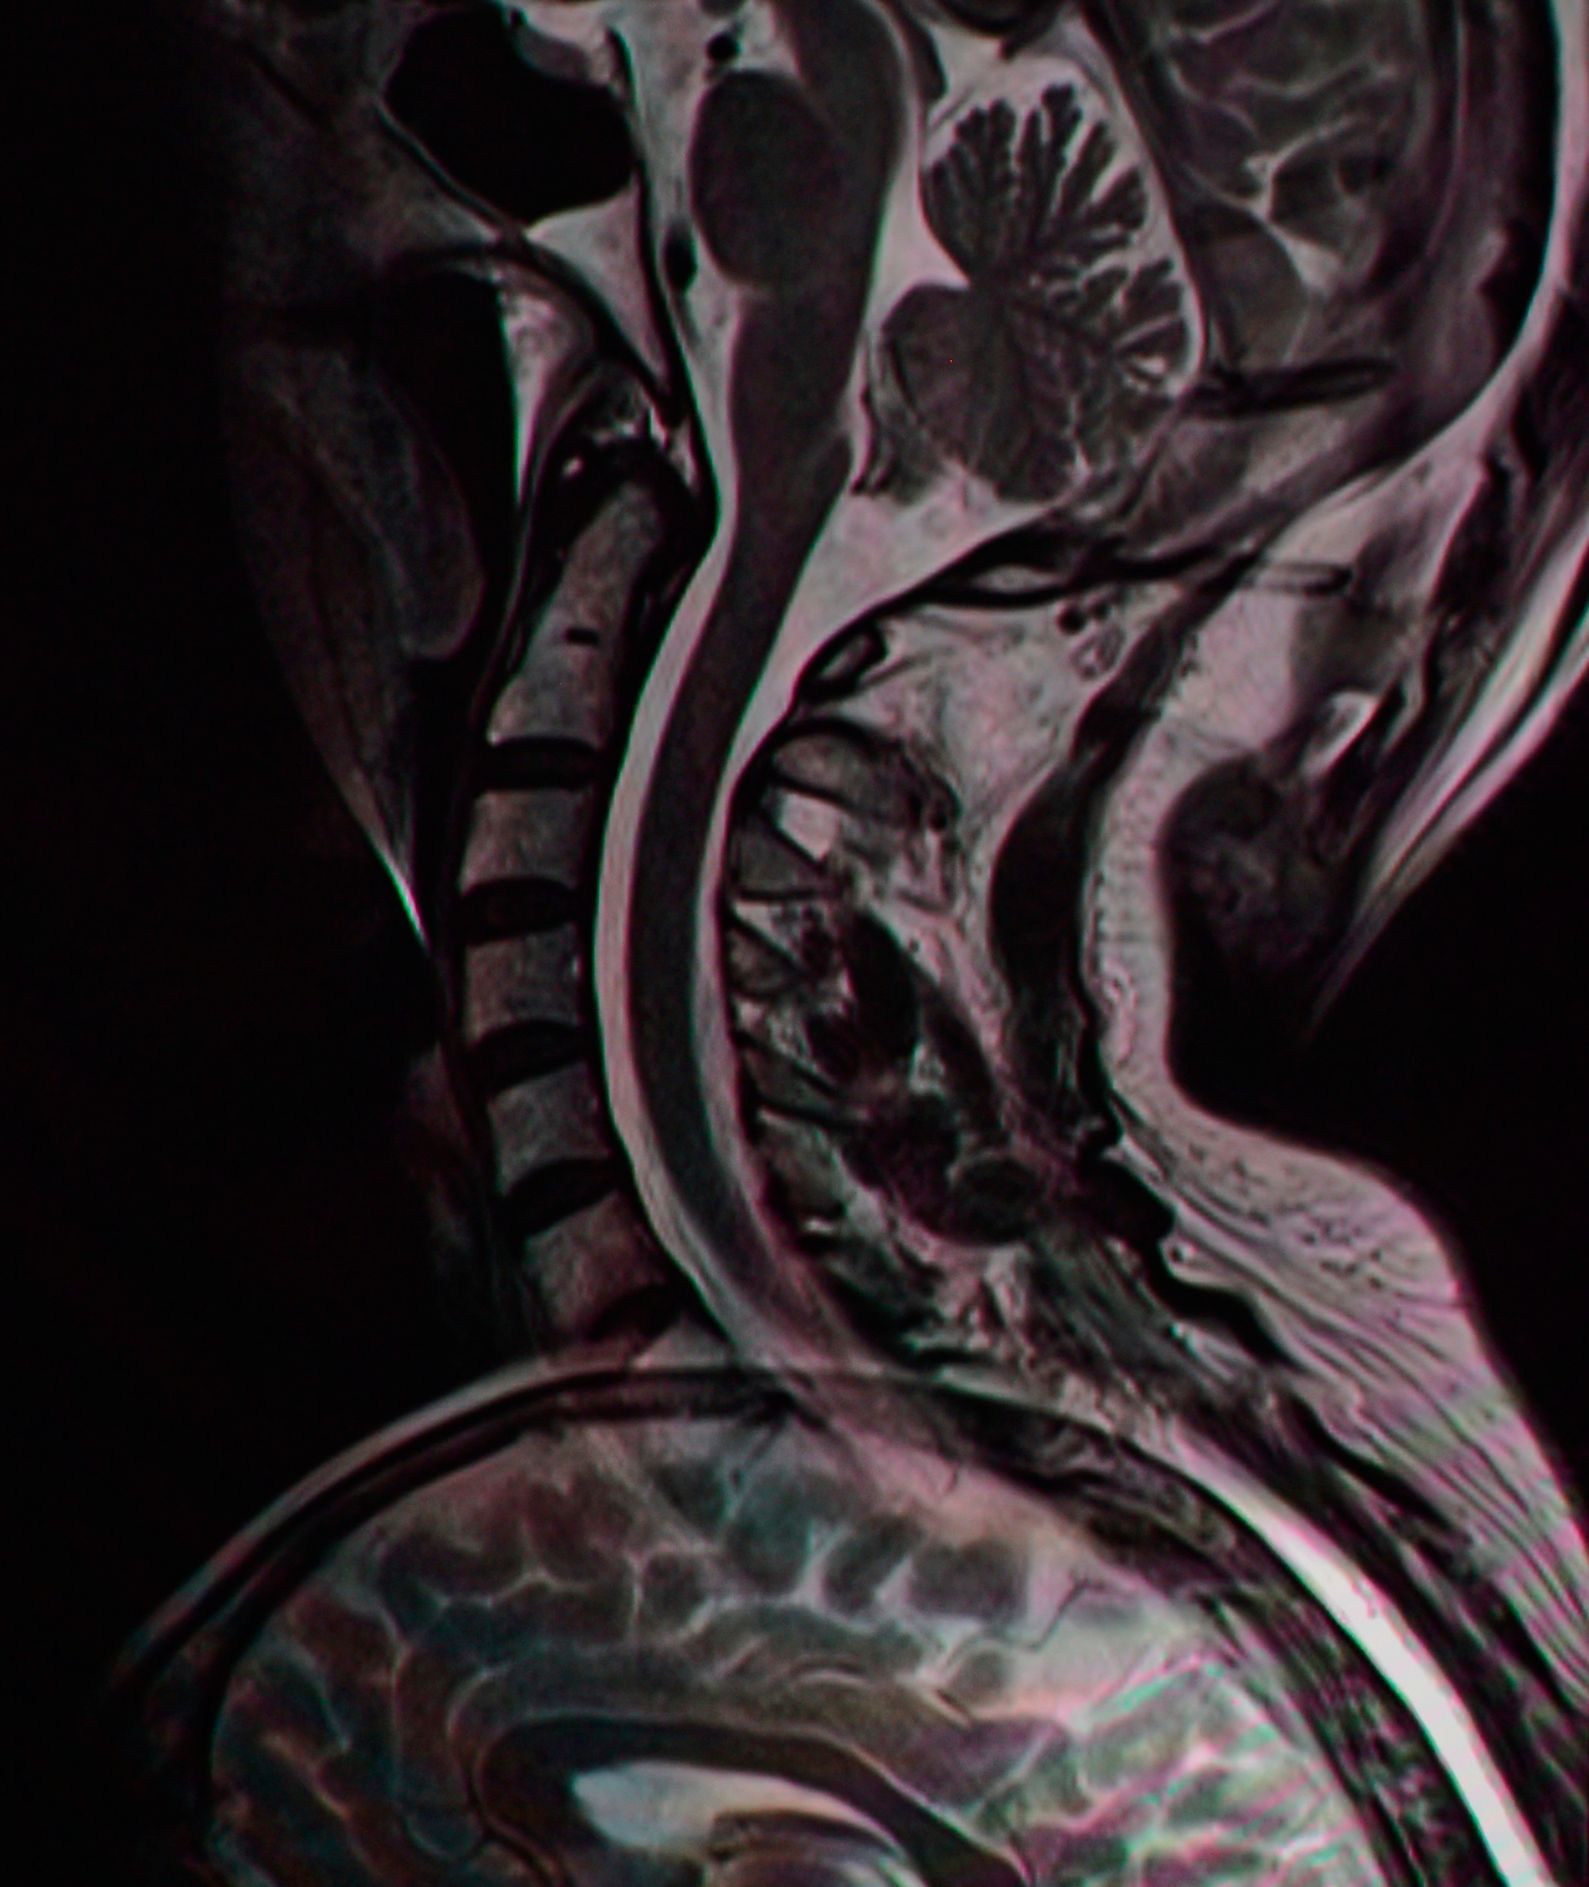

We offer applications training of MRI and CT systems to technologist. We use experienced registered trainers. In a training session, we accomplish protocol implementation, image optimization and technologist familiarization with the imaging scanner. Our goal is to create a positive experience where the technologist is able to effectively operate the system to create diagnostic images.